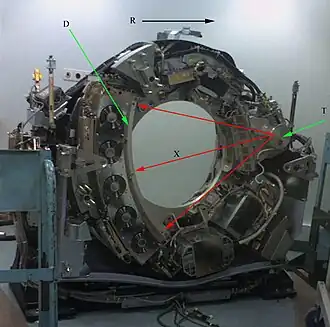

D: detectores de raio X; R: sentido de rotação; T: tubo de raio X; X: feixes de raio X

Para obter uma TC, o paciente é colocado numa mesa que se desloca para o interior de um anel de cerca de 70 cm de diâmetro. À volta deste encontra-se uma ampola de Raios-X, num suporte circular designado gantry. Do lado oposto à ampola encontra-se o detector responsável por captar a radiação e transmitir essa informação ao computador ao qual está conectado.